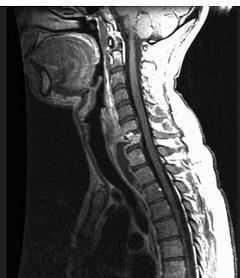

问题 男,41岁,颈痛,发热,请结合图像,选出最可能的诊断 ( )

选项 A、脊椎结核 B、椎间盘突出 C、脊柱转移瘤 D、椎体压缩骨折 E、化脓性脊柱炎

答案 A